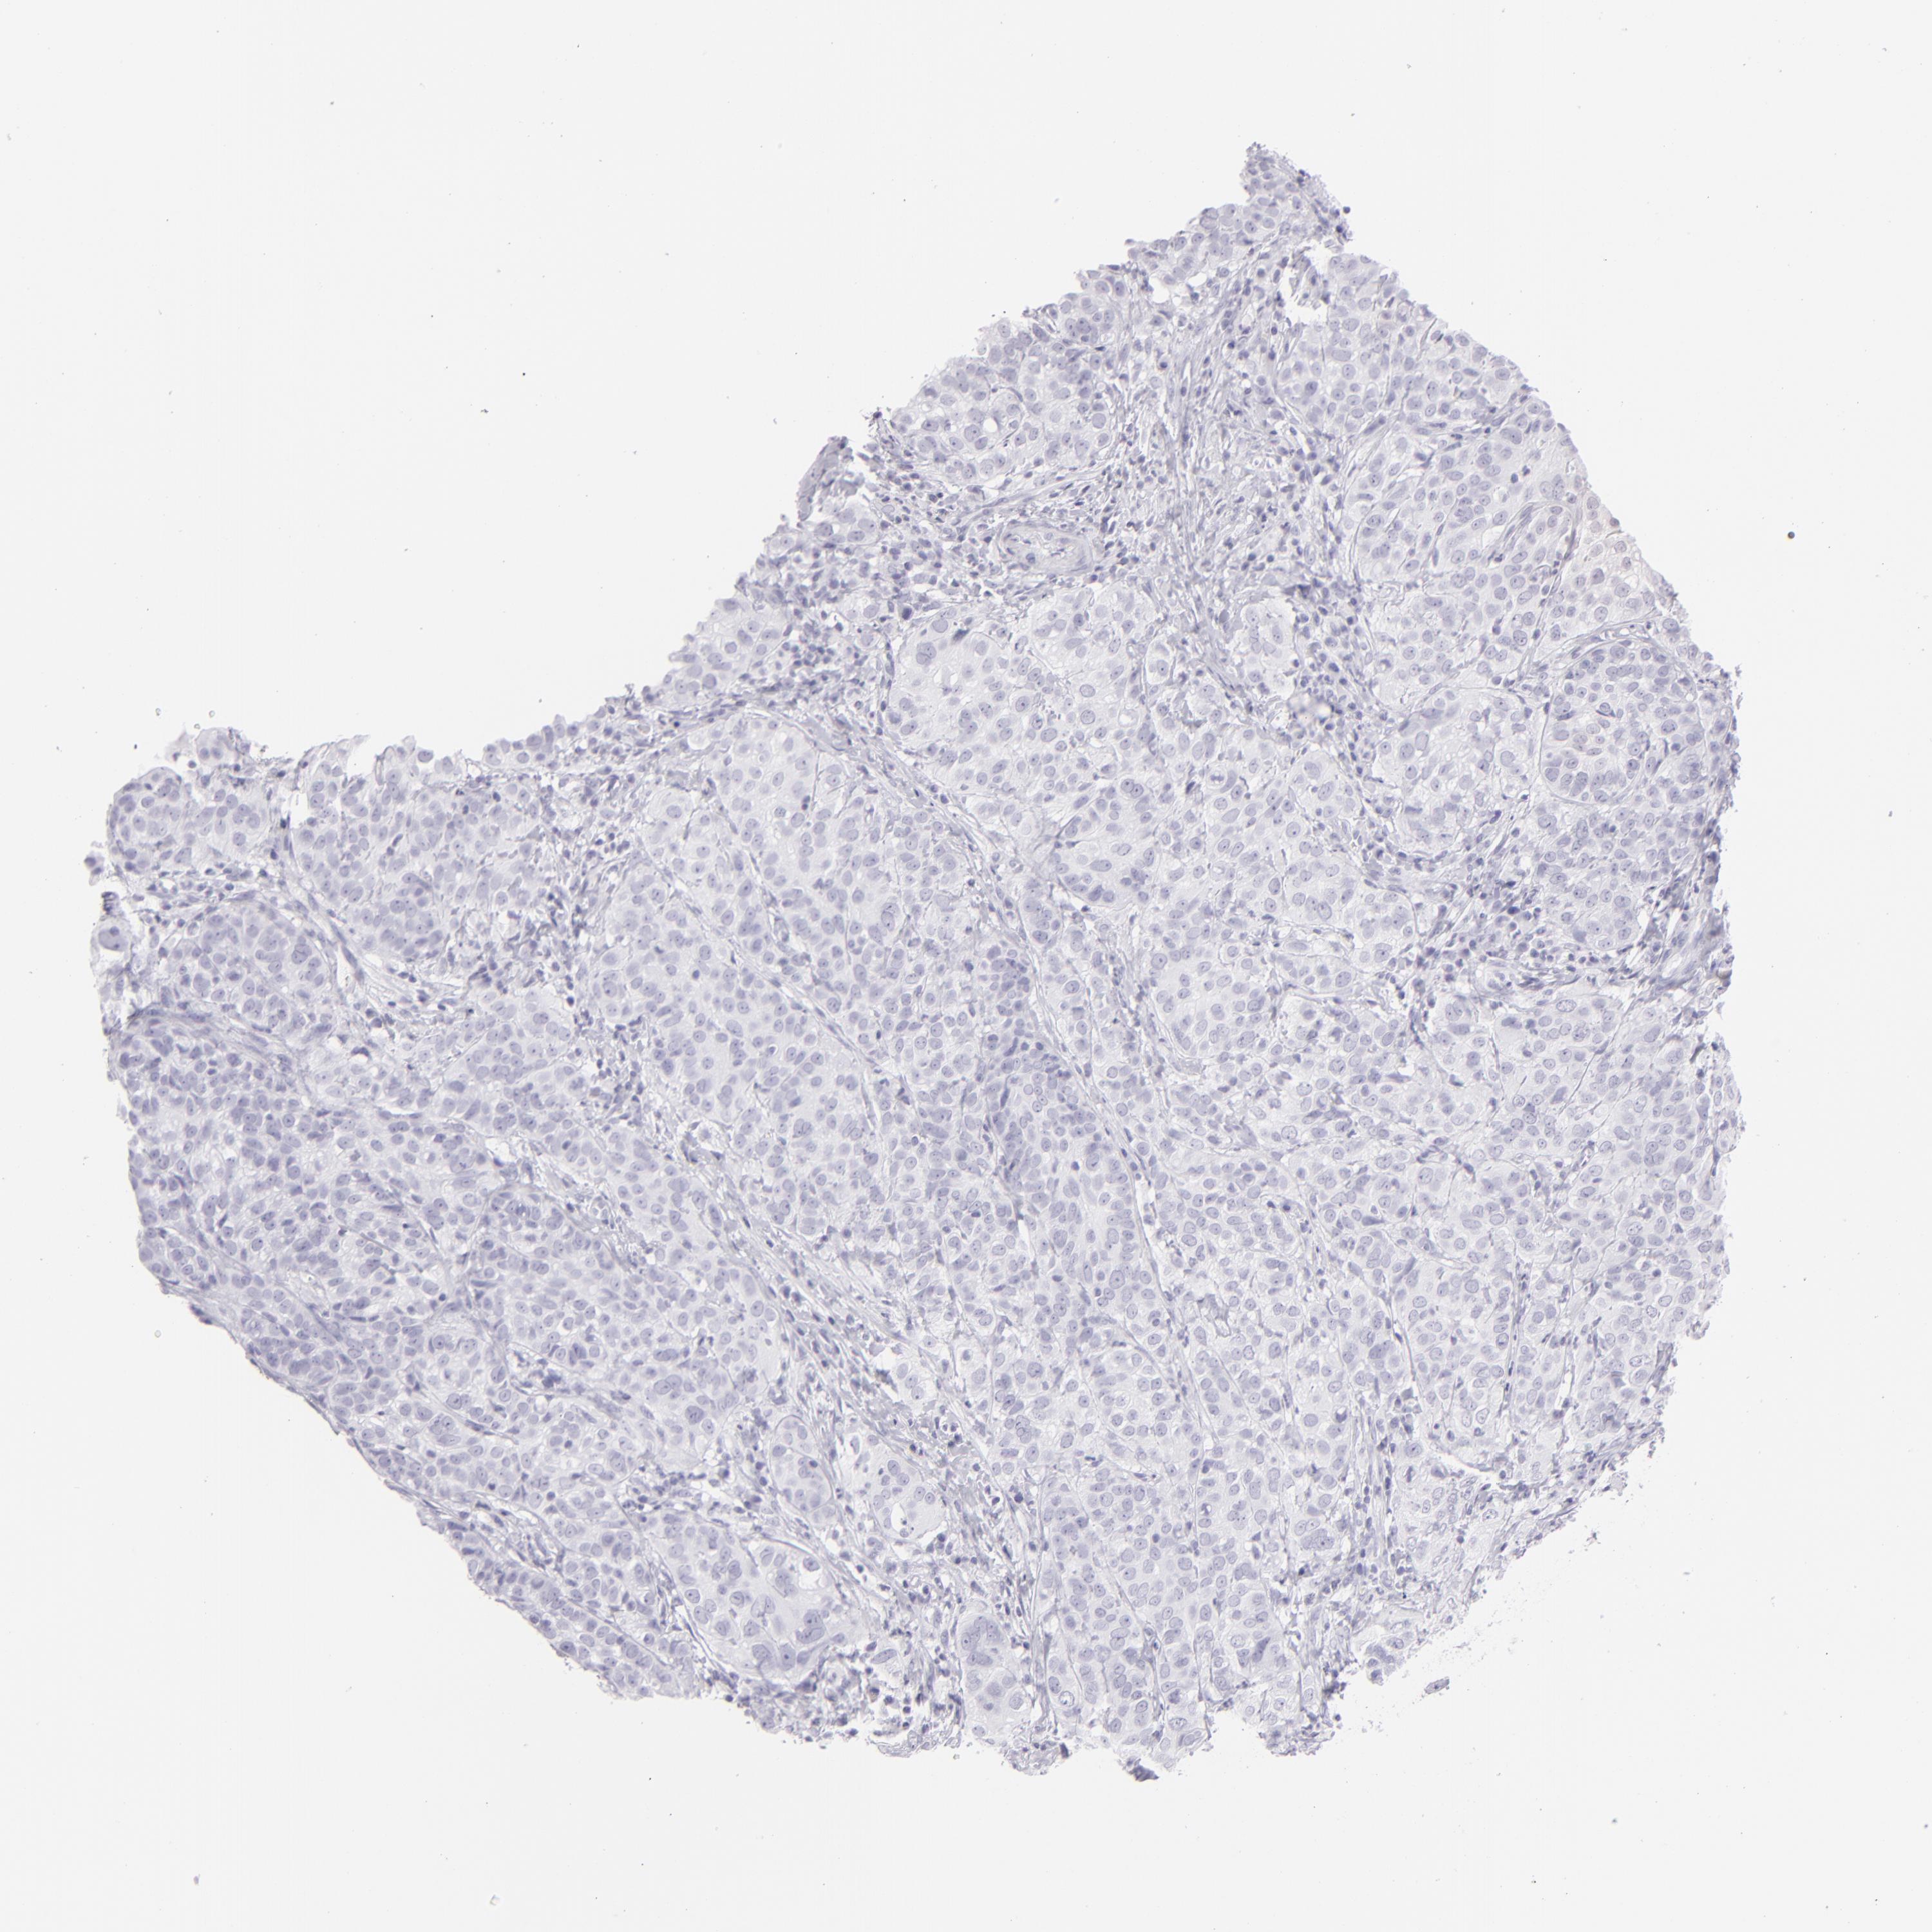

CERVICAL CANCER - Protein expressioni

A mouse-over function shows sample information and annotation data. Click on an image to view it in a full screen mode. Samples can be filtered based on level of antibody staining by selecting one or several of the following categories: high, medium, low and not detected. The assay and annotation is described here.

Note that samples used for immunohistochemistry by the Human Protein Atlas do not correspond to samples in the TCGA dataset.

Antibody stainingi

Antibody staining in the annotated cell types in the current human tissue is reported as not detected, low, medium, or high, based on conventional immunohistochemistry profiling in selected tissues. This score is based on the combination of the staining intensity and fraction of stained cells.

Each image is clickable and will lead to virtual microscopy that enables deeper exploration of all samples and also displays staining intensity scores, fraction scores and subcellular localization as well as patient and tissue information for each sample.

Antibody HPA030188

Antibody HPA030189

Antibody CAB002210

Squamous cell carcinoma, NOS

Adenocarcinoma, NOS